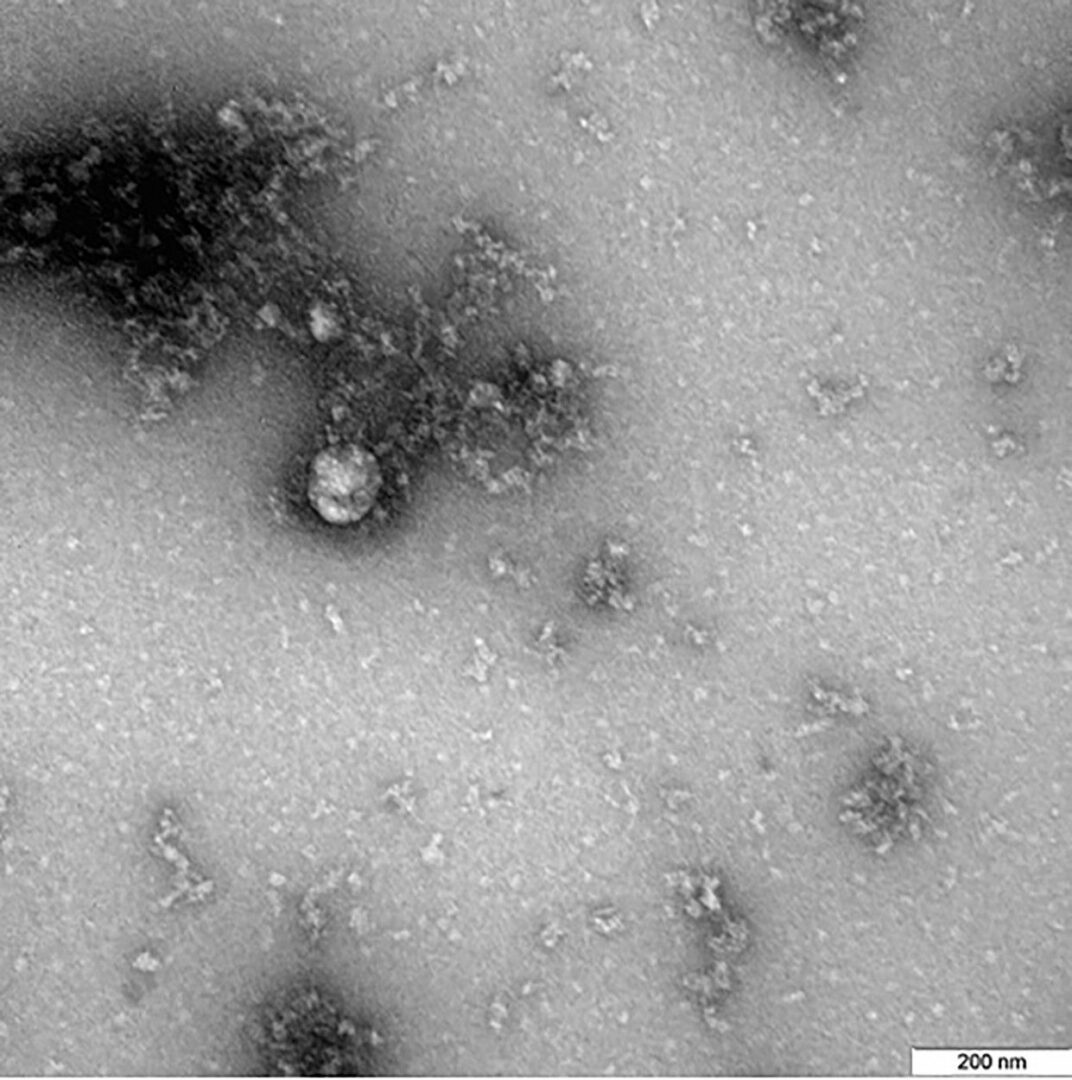

Aşa arată virusul la microscop

Potrivit celor de la Profimedia Images, care au și postat imaginea pe reţelele de socializare, bărbatul a reușit să fotografieze la microscop noua tulpină a coronavirusului, poza fiind realizată într-un centru de cercetare din Siberia, scrie Protv.ro.